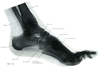

足の骨